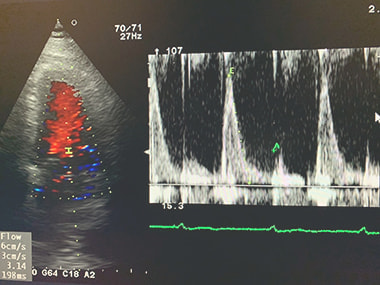

心エコー検査:

心臓が正常に働いているかどうかを調べる検査です。心臓の大きさ、動き、

弁の状態、血液の流れなどを調べ、弁膜症、心筋症、心不全などを診断します。

心臓